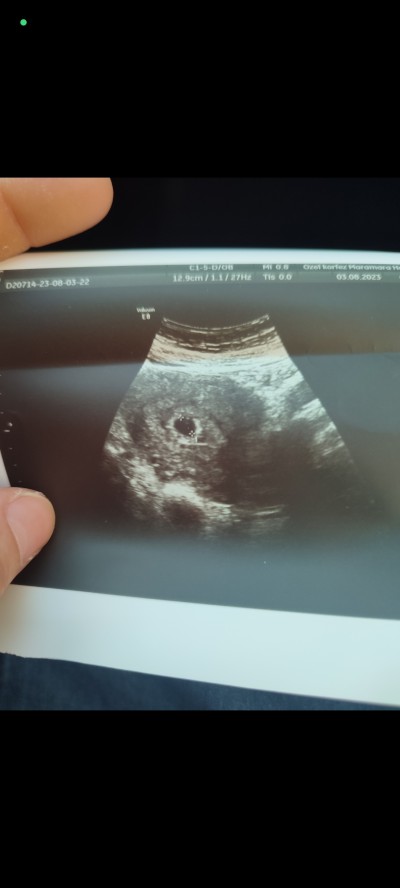

imageaay bende merak ettim şimdi kese şekli nasıl tam çözemedim sizce kız mı erkek mi

31 Ağustos 2023 (284 puan) yorumladı

Ayy inşallah önce sağlıklı olsun da ama kız çok istiyorum 29 haftalık bebeğimi kaybettim ocak ayında bir takım hazırlıklarda yapmıştım normalde cinsiyet tabi fark etmez ama içim kız da kaldı :(

Yuvarlak kese